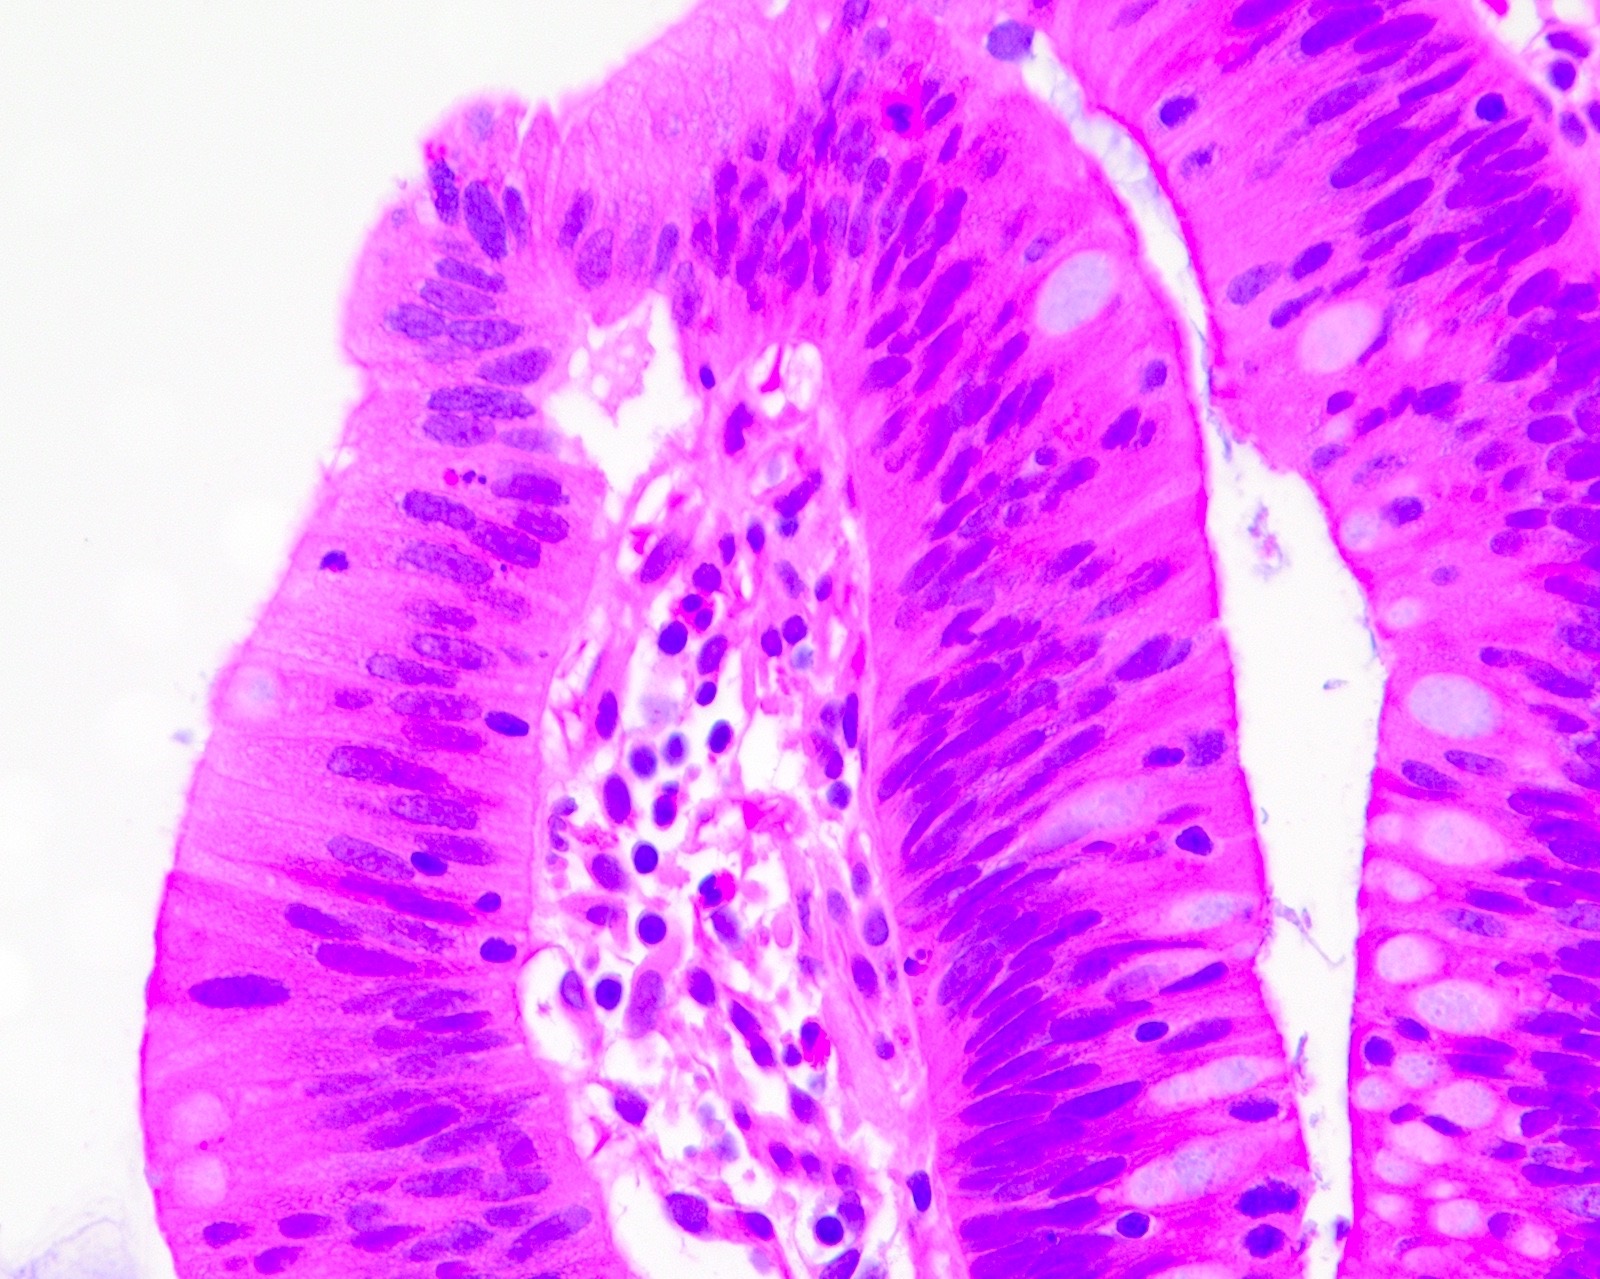

Microscopic (histologic) description

- Polypoid colonic mucosa covered with dysplastic epithelium comprised of hyperchromatic, elongated nuclei arranged in a pseudostratified manner

- Dysplasia is typically low grade but may also be high grade, with architectural (cribriforming, luminal necrosis) and cytologic changes (vesicular chromatin, nucleoli, loss of basal polarity)

- Abrupt transition from normal to dysplastic mucosa is commonly present

- Variable amounts of mucin loss

Microscopic (histologic) images

Contributed by Andrew L.J. Dunn, M.D. and Christopher Hartley, M.D.

Contributed by @Andrew_Fltv and @liverwei on Twitter